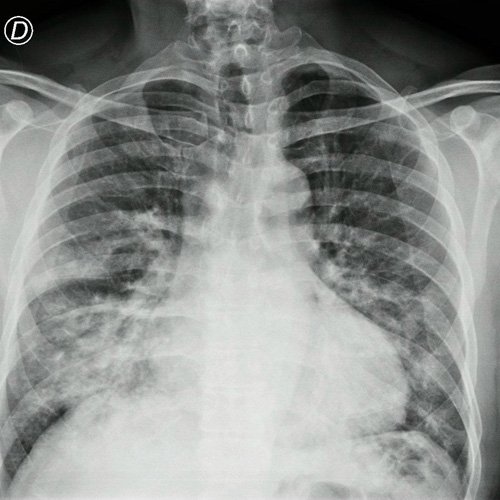

- Radiografía de tórax frente/perfil (Dia 0): rotada, bien inspirada, índice cardiotorácico impresiona conservado , se observa infiltrado parenquimatoso a nivel medio basal de campo pulmonar derecho e izquierdo, senos costofrénicos impresionan libres..

Radiografía de tórax frente y perfil

Radiografía de tórax frente y perfil